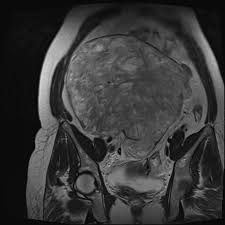

Broad ligament fibroids are benign smooth muscle tumours that arise from the broad ligaments, a fold that supports the uterus. They are a type of extrauterine fibroid, which means that, unlike typical fibroids that develop within the uterine wall or cavity, these grow outside the uterus, specifically between the layers of the broad ligament.

Broad ligament fibroids are divisible into two types such as true broad ligament fibroids and false broad ligament fibroids. True broad ligament fibroids come from the muscle fibres of the broad ligament itself, not from the uterus. On the other hand, false broad ligament fibroids start in the uterine muscle but grow sideways into the broad ligament, making it look like they came from there.